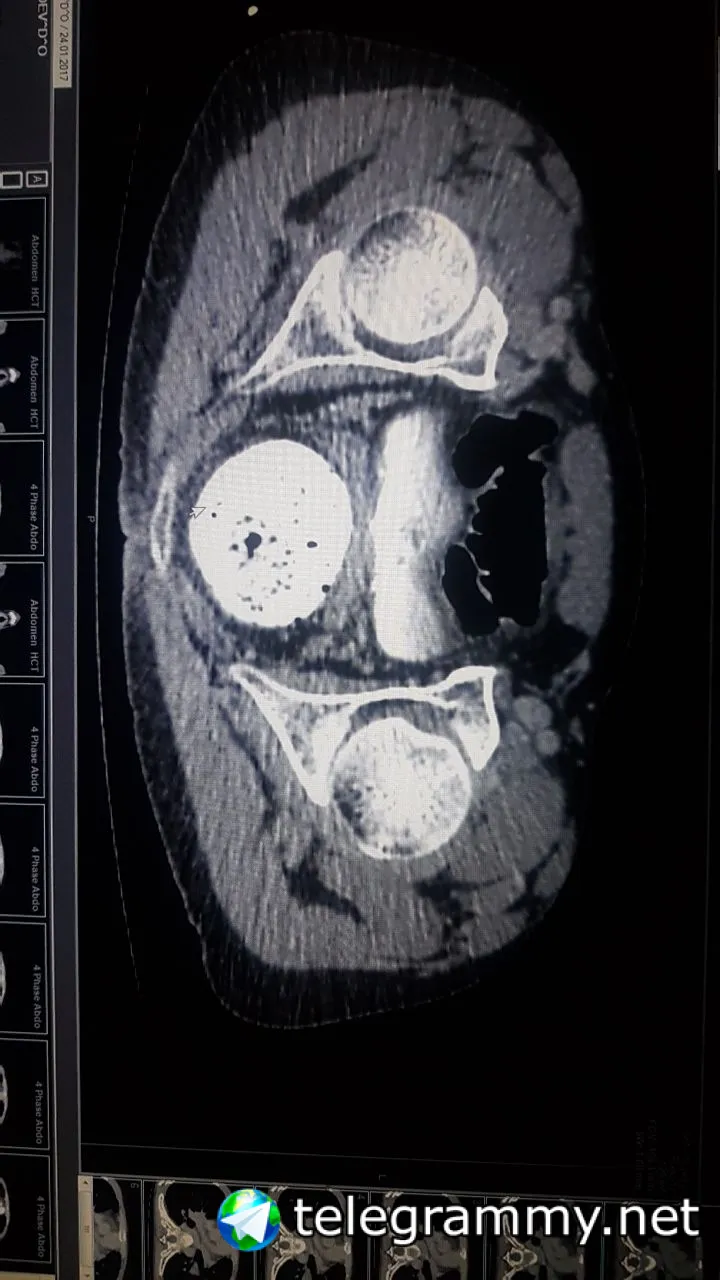

Это последний прогон КТ с контрастом йода. Как так возожно что контраст за пару минут пройдя по венам попал в паховую область явно не в составе сосуда? Или что как это?

Все нормально. Барий пили?

В том и дело что нет, это йод внутривенно. Хотя барий пил за два дня до этого